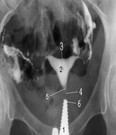

HSG ya da rahim filmi uterus boşluğunu ve fallop tüplerin açık olup olmadığını değerlendirmede kullanılan en geleneksel tanı yöntemidir. Normal uterin kavite üçgen şeklinde, simetrik ve düzgün konturludur ve verilen kontrast madde her iki tüpten geçerek karın boşluğunda dağılır. Tüplerin açık olup olmadığının yanı sıra çeşitli uterin anomaliler, polip ve myomlar, rahim içi yapışıklıklar HSG de karakteristik bazı görünümler oluştururlar.